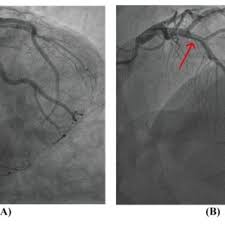

- 혈관조영술(Cerebral Angiography): 혈관조영술은 혈관 내부 구조를 자세하게 시각화하기 위해 사용됩니다. 이 절차는 모야모야병을 진단하는 가장 확실한 방법 중 하나입니다.

2. 혈관 조영술 (Cerebral Angioplasty): 혈관 조영술은 혈관 내부의 협착을 개선하기 위해 사용됩니다. 이 절차에서는 혈관 내부에 스텐트(Stent)를 배치할 수도 있습니다.